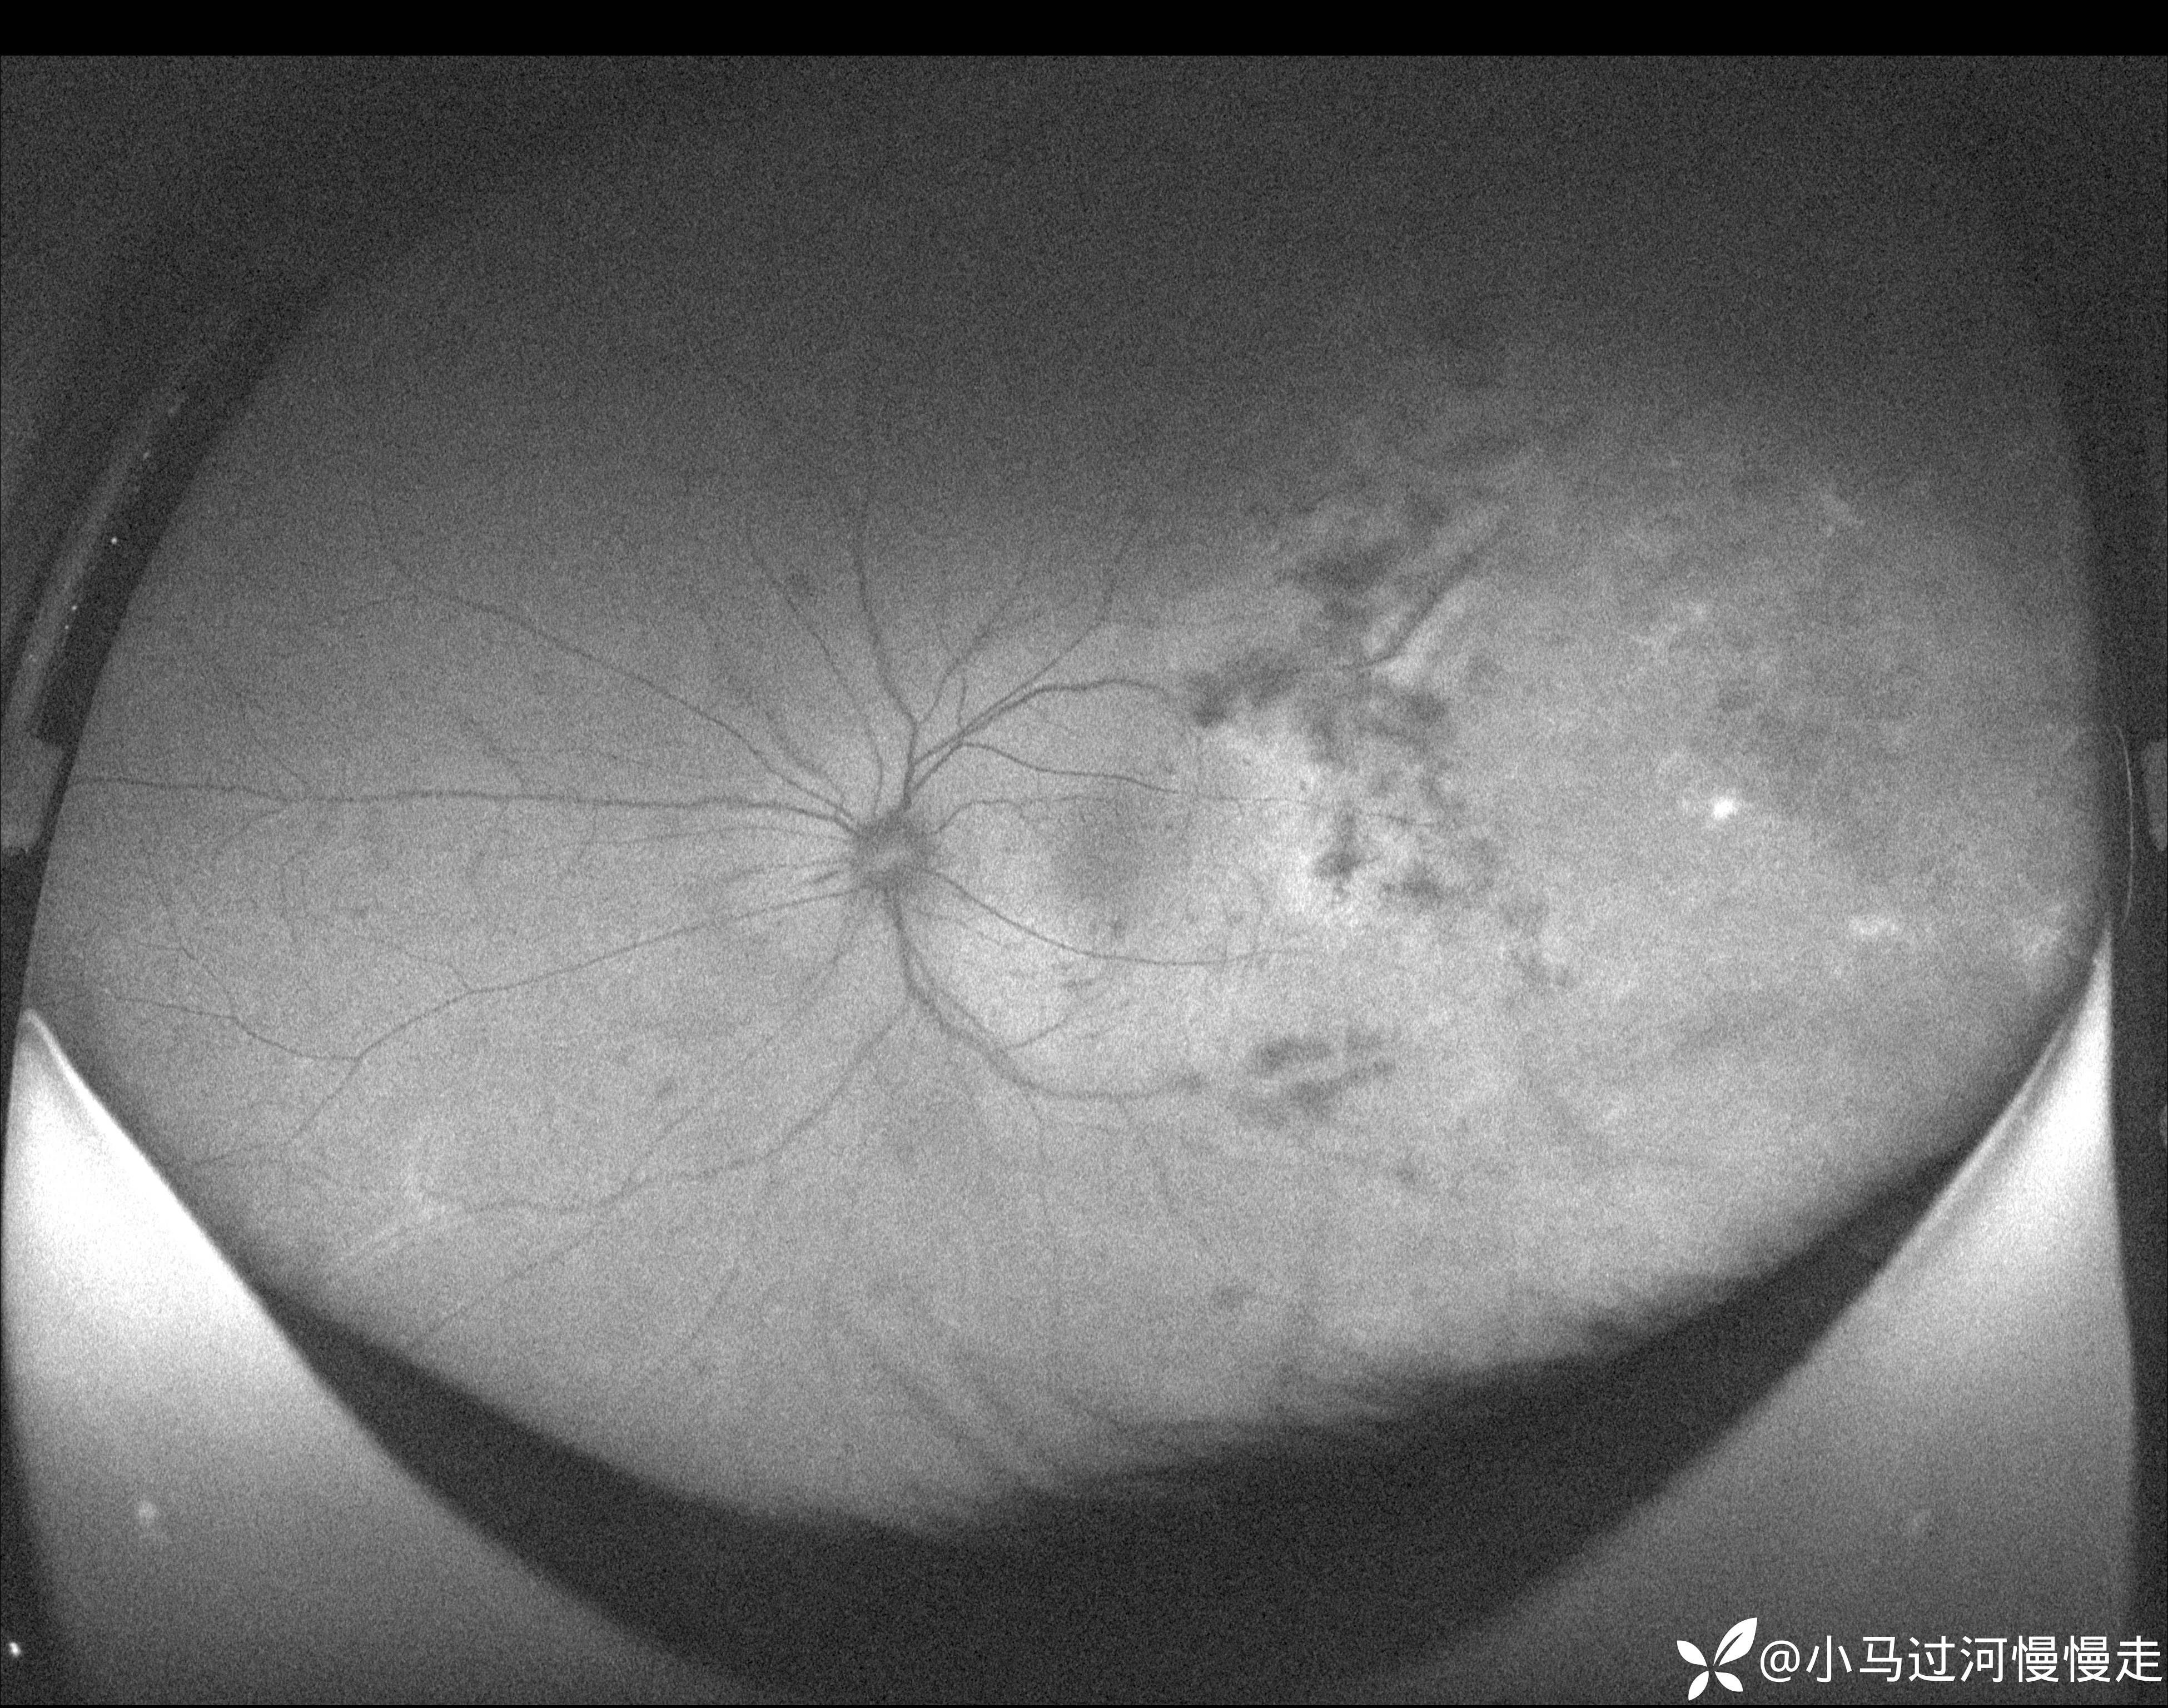

患者是HIV感染者,就诊时外院已经确诊了AIDS。右眼底正常,左眼底表现为霜枝样静脉炎及颞侧"番茄炒蛋"样病变,病变中心可见坏死灶:

当时正在试用视微SSOCT,记录了左眼颞侧病变的影像。